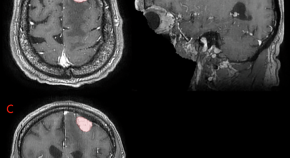

Brain imaging refers to the usually non-invasive or minimally invasive techniques that enable imaging the structure or function of the brain. Brain imaging techniques take advantage of X-rays, radioactive labelling, magnetic fields induced by the brain’s electric activity, or optical absorption or paramagnetic properties of haemoglobin.